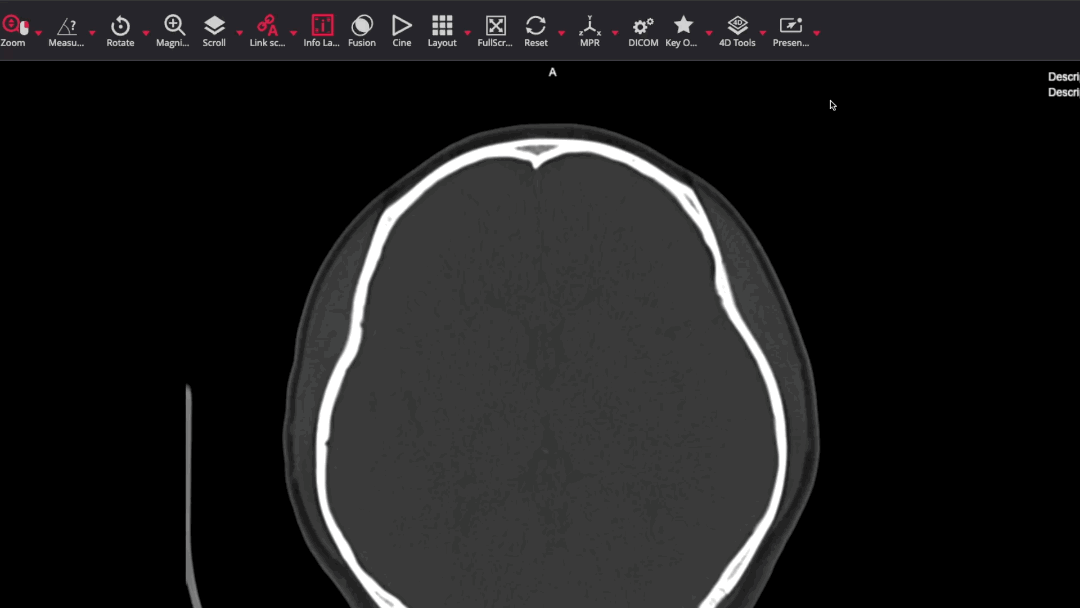

- Hot Seat: Nominate a learner to present a case by sharing their screen and review using the DICOM viewer.

- Presenter Tools: Encourage the use of tools like fading arrows and lines to highlight findings.